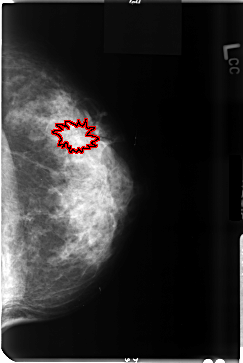

B_3495_1.LEFT_CC

LEFT_CC LINES 4712 PIXELS_PER_LINE 3152 BITS_PER_PIXEL 12 RESOLUTION 50 OVERLAY

FILE: B_3495_1.LEFT_CC.OVERLAY

TOTAL_ABNORMALITIES 1

ABNORMALITY 1

LESION_TYPE CALCIFICATION TYPE PUNCTATE DISTRIBUTION CLUSTERED

LESION_TYPE MASS SHAPE ARCHITECTURAL_DISTORTION MARGINS ILL_DEFINED

ASSESSMENT 4

SUBTLETY 2

PATHOLOGY BENIGN

TOTAL_OUTLINES 1

BOUNDARY